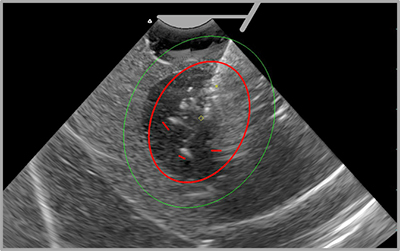

close-up ultrasound of uterine fibroids

The Sonata SMART Guide displays a real-time graphic overlay on the live ultrasound image.

The Sonata System includes a proprietary graphical user interface (SMART Guide), enabling the surgeon to target fibroids and optimize treatment. The SMART Guide displays a real-time graphic overlay on the live ultrasound image, providing safe targeting and delivery of radiofrequency energy. The graphic overlay is controlled by the surgeon to determine the size and location of the ablation zone, safety borders, and the duration of radiofrequency energy delivery.